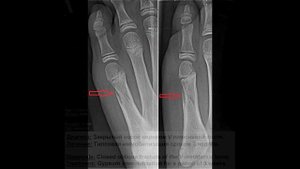

Перелом пятой плюсневой кости: симптомы, лечение, сроки восстановления Часть 2, первая часть в перво